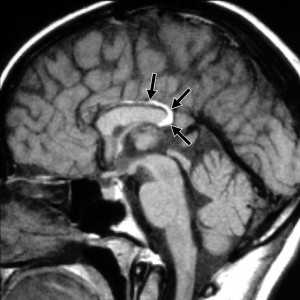

Киста кармана Ратке представляет собой редко встречающееся образование из остатков эмбриональной эктодермы (щель Ратке), расположенное между долями гипофиза. Выявляется в любом возрасте, но чаще в 50-60 лет. Клинические проявления связаны с масс-эффектом. При головного мозга выявляется небольшая (3-5 мм) киста с четким контуром, без отека вокруг, однородная по структуре. Сигнал зависит от содержимого. При серозном содержимом сигнал типично жидкостный, при мукоидном киста светлая на Т1-взвешенных МРТ. В редких случаях киста достигает больших размеров и даже выходит за пределы седла. Стенка кисты иногда усиливается при контрастировании.

МРТ головного мозга. Т2-взвешенная корональная МРТ. Киста кармана Ратке.

Киста кармана Ратке представляет собой редко встречающееся образование из остатков эмбриональной эктодермы (щель Ратке), расположенное между долями гипофиза. Выявляется в любом возрасте, но чаще в 50-60 лет. Клинические проявления связаны с масс-эффектом. При МРТ головного мозга выявляется небольшая (3-5мм) киста с четким контуром, без отека вокруг, однородная по структуре. Сигнал на МРТ головного мозга зависит от содержимого. При серозном содержимом сигнал типично жидкостный, при мукоидном киста светлая на Т1-взвешенных МРТ головного мозга. В 70-80% случаев внутри кисты выявляется неконирастирующийся узелок («пятно») - признак патогномоничный для кисты кармана Ратке. В редких случаях киста достигает больших размеров и даже выходит за пределы седла. Стенка кисты иногда усиливается при МРТ головного мозга с контрастированием. Дифференциальная диагностика при МРТ головного мозга должна проводиться с арахноидадьной и эпидермоидной кистами, тератомой, кистозной аденомой гипофиза и краниофарингиомой. Иногда при МРТ головного мозга киста кармана Ратке напоминает “пустое” турецкое седло. При маленьких размерах кисты ее на до дифференцировать на МРТ с микроаденомой гипофиза.

![Ratke cleft cyst]()

МРТ головного мозга. Т1-взвешенная сагиттальная МРТ. Киста кармана Ратке.